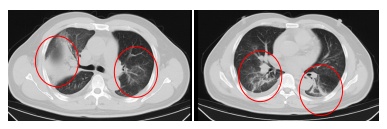

发热门诊医生详细询问顾先生的既往病史,并为其进行细致的体格检查。胸部CT结果显示,顾先生的双肺存在大面积的炎症病变。

鉴于顾先生的肺部感染情况较为严重,门诊医生立即将其收住感染科病房接受进一步治疗。